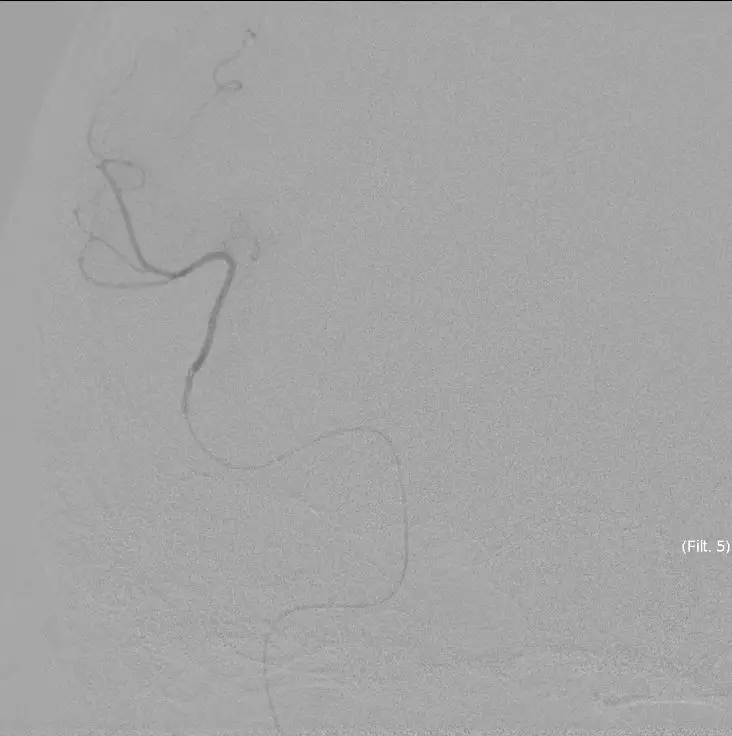

再次观察10MIN后

16:30分

手术结束

持续替罗非班4ml/H静脉泵入